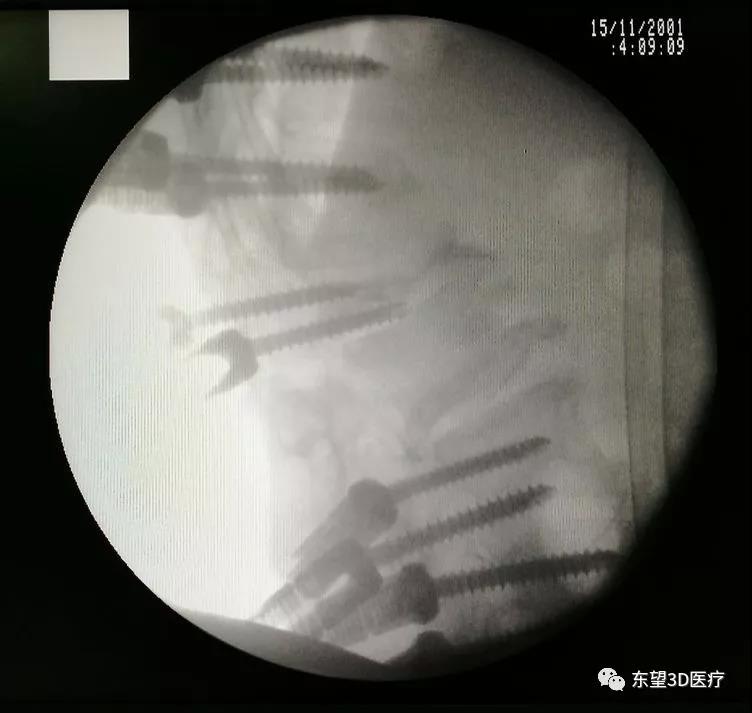

術中置釘、減壓見硬膜囊脊髓搏動良好

\

X線透視椎弓根釘位置準確